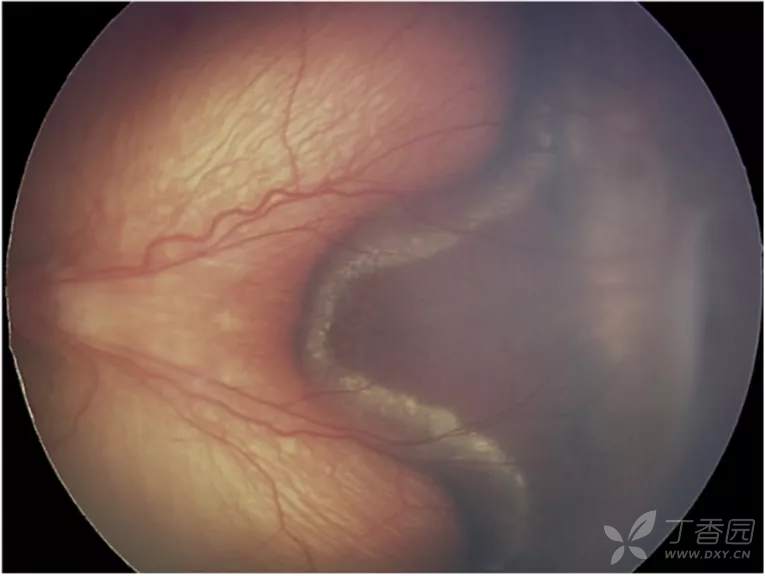

06、急性早产儿视网膜病变4期:部分视网膜脱离

图. 4B期黄斑脱离。

图. 4B期视网膜脱离伴视网膜下出血和黄斑脂质渗出。

图. 火山状4B期,后极部ROP患眼,病理性新生血管收缩导致血管化视网膜脱离形成火山状结构。

急性ROP4期OCT图像

图. 4B期视网膜脱离:OCT可见中心凹视网膜脱离(星号),在检眼镜检查中很难识别。